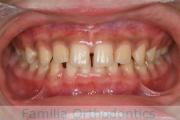

顎が後退しているので前に出したい、ということで来院された、骨格性下顎後退の大変な難症例です。スプリント療法から顎変形症の治療を行い、6年近い年月と80回以上の通院が必要でした。

外科的矯正治療には、矯正治療単独で行った場合のリスクや副作用に加えて、外科手術のもつリスクがあります。

全身麻酔や入院の必要性、術後の疼痛や顔の腫れ、手術部位周囲の感覚麻痺などがそれにあたります。